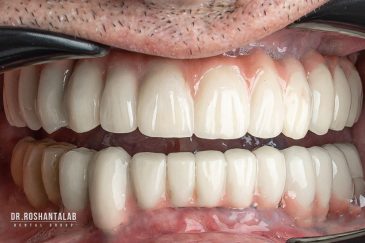

طراحی لبخند هالیوودی با متدهای لمینت سرامیکی دندان و کامپوزیت ونیر در کنار اصلاح فرم، خدمات بلیچینگ و روکش دندان، زیبایی چهره شما را تکمیل میکند.ترمیم دندان

تجربه کاشت دندان دیجیتال و بدون درد در ۳ دقیقه! استفاده از برترین برندها زیر نظر جراح، با هزینه مناسب و خدمات کامل از کاشت دندان تا روکشارتودنسی دندان

انتخاب بهترین متخصص ایمپلنت که به تکنیکهای روز دنیا مسلط باشد، تضمینکننده سلامت فک و زیبایی لبخند شماست. در کلینیک دندانپزشکی دکتر روشنطلب، ما با بهرهگیری از تجهیزات دیجیتال در ۵ شعبه فعال (تهران، اصفهان، رشت و استانبول ترکیه)، خدمات تخصصی کاشت ایمپلنت دندان را برای بیمارانی که کیفیت و دقت برایشان اولویت دارد، ارائه میدهیم. در این متد، پروسه درمان با ظرافت بالا انجام شده؛ راهکاری ایدهآل برای کسانی که به دنبال درمان بدون درد با بالاترین نرخ موفقیت هستند.